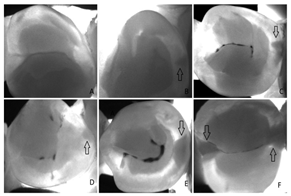

| Cone-beam Computed Tomography (CBCT) | [19,38,53,64,67,93,97,98,99,100,101,102,103,104] | Endodontics, orthodontics, implant, oral surgery, and oral medicine | ![]() | High resolution 3D volumetric data. |